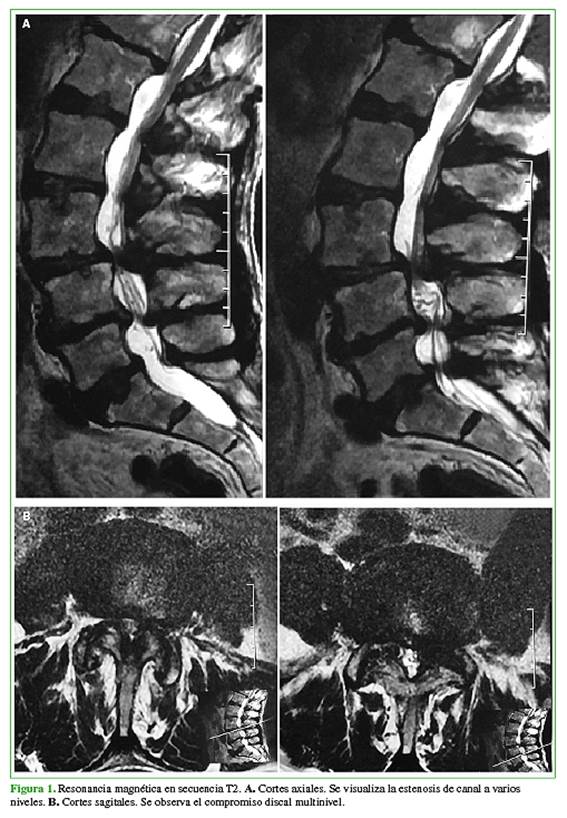

Los cuatro pacientes de la serie tenían estenosis de canal lumbar multinivel en las imágenes por resonancia magnética (Figura 1) y dolor radicular de larga data, y claudicación en la marcha sin inestabilidad segmentaria, que fueron evaluados en las radiografías en flexión y extensión.